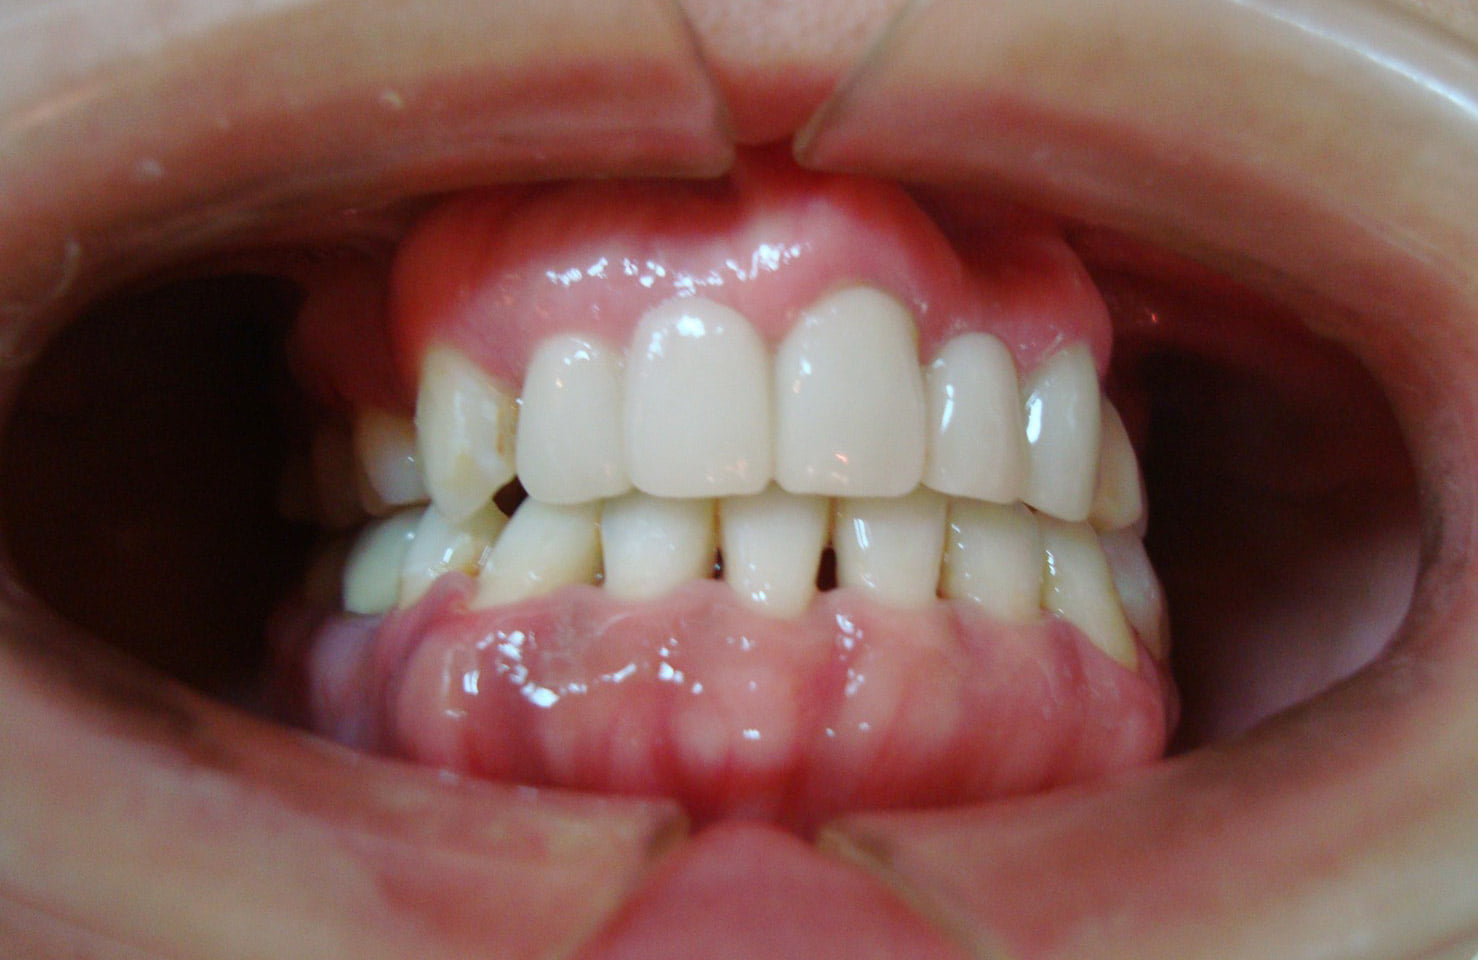

牙齒矯正